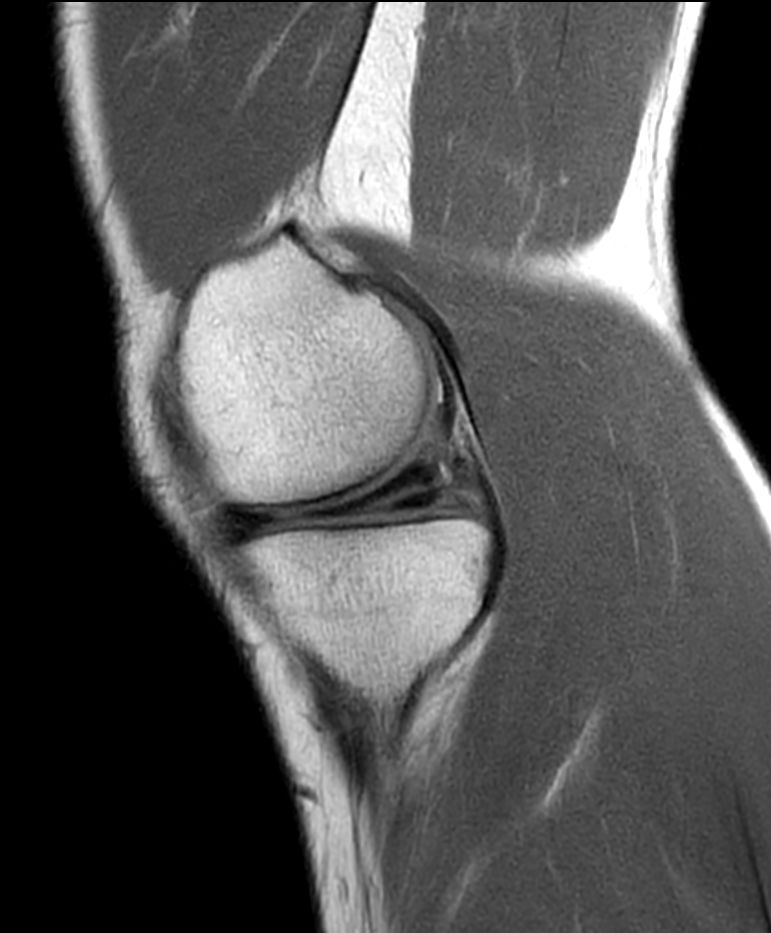

PDw TSE - Compressed SENSE